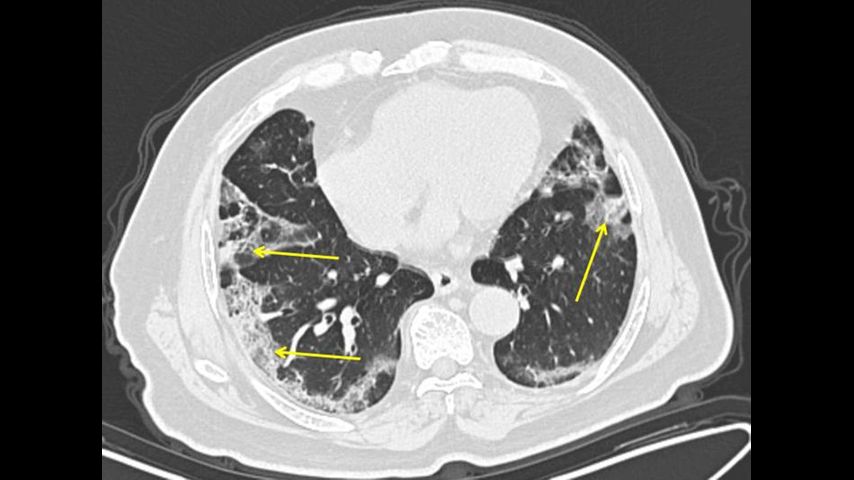

Doctors at New York’s Mount Sinai Health System analyzed 121 chest CT scans shared by colleagues in China and spotted something unusual.

Healthy lungs look mostly black on medical scans because they’re full of air. An early infection with bacterial pneumonia tends to show up as a white blotch in one section of one lung. Pneumonia caused by a virus can show up as hazy patches that go by a weird name -- “ground glass opacities.”

In people who get COVID-19 pneumonia, that haze tends to cluster on the outside edge of both lungs, by the ribs, a distinctive pattern, said Dr. Adam Bernheim, a radiologist at Mount Sinai.

As infection worsens, the haze forms rounder clusters and gradually turns more white as the air sacs become increasingly clogged.